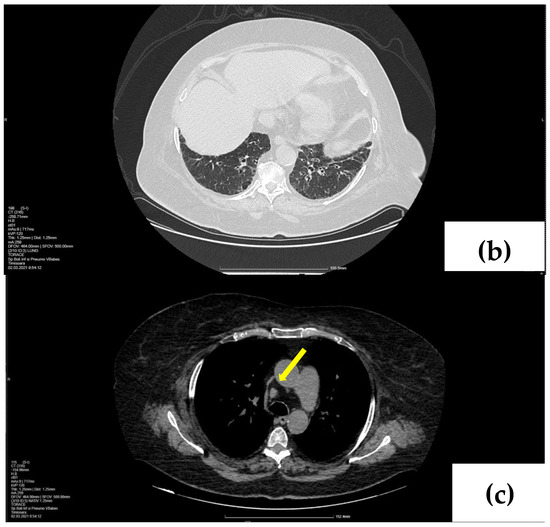

2. Case Presentation

2.1. Laboratory, Radiological, and Histological Examinations

2.2. Treatment and Outcome